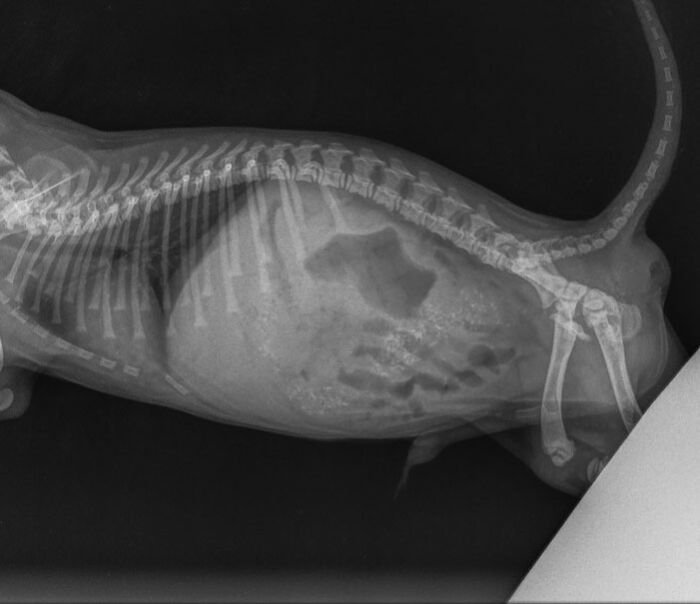

Tooshie is a small, 5-week-old Australian Cavoodle puppy, whose life has just begun – and is already under serious threat. A backyard breeder brought the puppy to Warwick Veterinary Hospital in Perth, Australia, complaining of his poor health – the employee of the clinic, who received the tiny patient, was told that he was vomiting and bloated.

The first thing practice manager Kate Doyle tried to do was to take his temperature, and then she made a really unexpected discovery. It turned out that the puppy simply had nowhere to insert a thermometer – after all, he had no anus. Yes, it turned out that Tooshie was born with an incredibly rare defect – anal atresia.

It turned out that Tooshie was born with atresia ani – an extremely rare case in which the puppy has no anus

This is a very rare situation – according to statistics (and a similar disease was first recorded in 1999), only 119 cases out of 1,624,499 dogs have been observed. At the same time, anal atresia is most often found in girl puppies. The peculiarities of puppy development allow them to live up to four weeks with anal atresia without much damage – but then the problems inevitably begin.